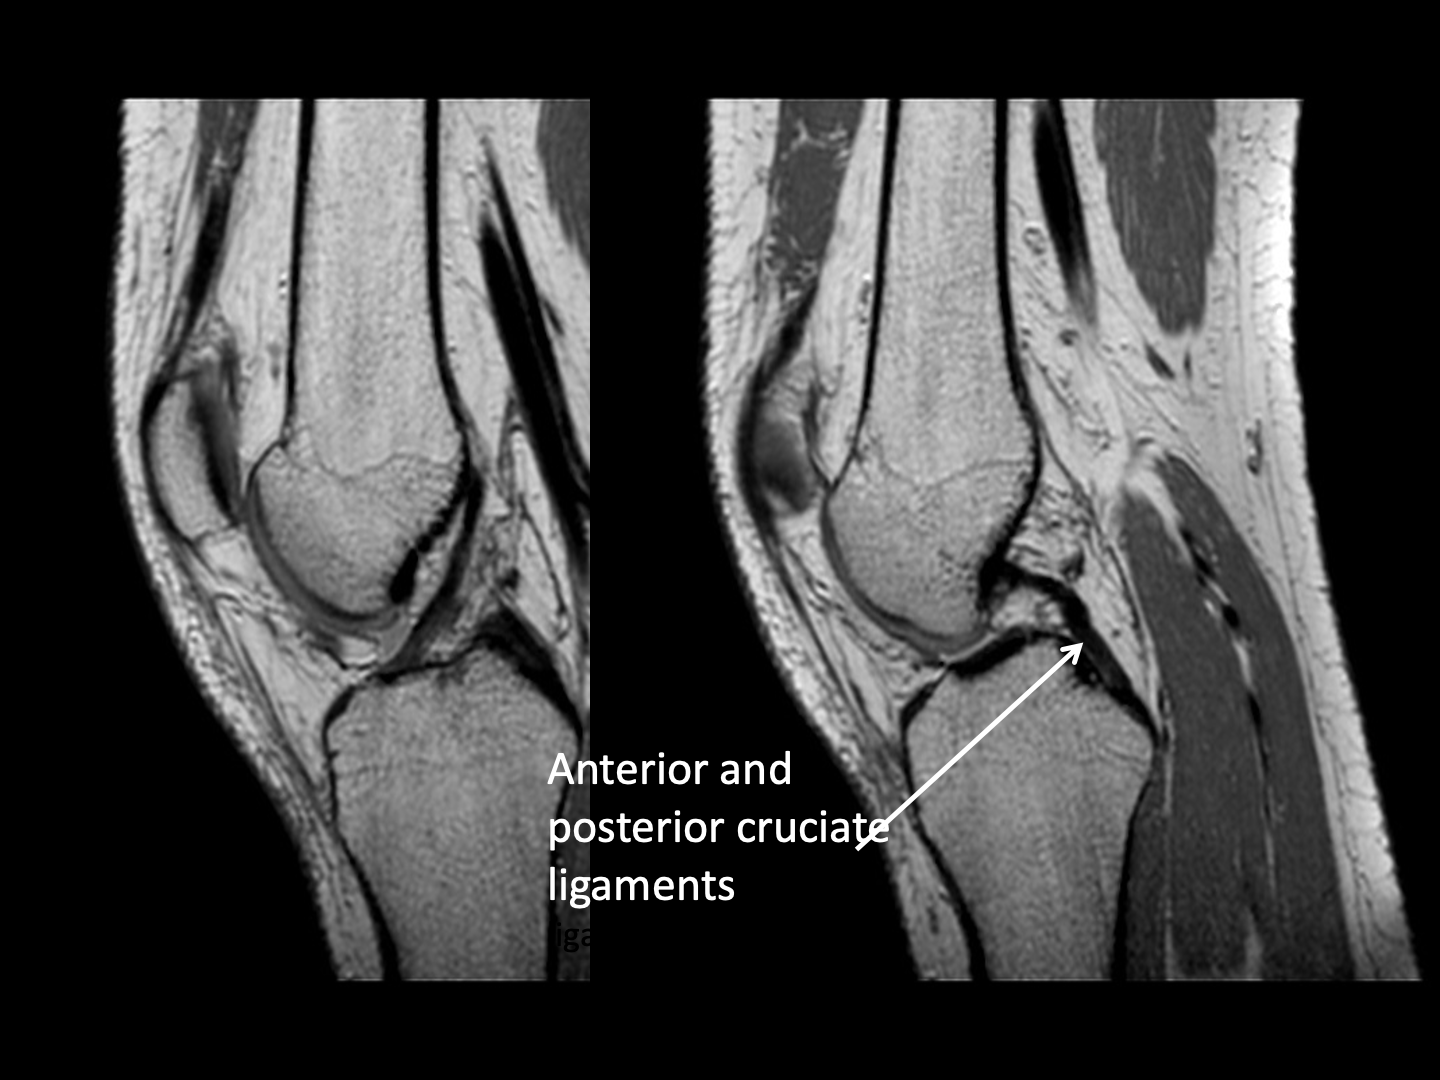

MRI is also very useful for demonstrating injury to soft tissues such as muscle, tendons and ligaments and is particularly useful in knee injuries.

- MRI is the best examination for sports injury.

- Meniscal and ligamentous tears (e.g. in the knee)